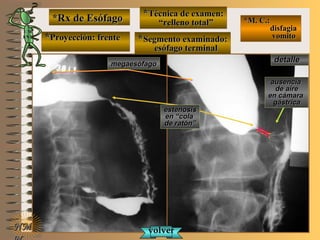

*Rx de Esófago*Rx de Esófago

**Proyección:Proyección:

**Técnica de examen:Técnica de examen:

**Segmento examinado:Segmento examinado:

*M. C.:*M. C.:

disfagiadisfagia

vomitovomito

NMNM

detalledetalle

frentefrente

““relleno total”relleno total”

esófago terminalesófago terminal

A-A-El examen es normal o patológico?El examen es normal o patológico?

Examen patológico de esófago toráxico conExamen patológico de esófago toráxico con

técnica de relleno total en proyección de frentetécnica de relleno total en proyección de frente

B-B-La patología es congénita o adquirida?La patología es congénita o adquirida?

Patología adquiridaPatología adquirida

C-C- Dicha patología es orgánica, funcional o mixta?Dicha patología es orgánica, funcional o mixta?

Patología adquirida orgánicaPatología adquirida orgánica

D-D-La misma es neoplásica o no neoplásica?La misma es neoplásica o no neoplásica?

Patología adquirida orgánica no neoplásicaPatología adquirida orgánica no neoplásica

E-E-Puede describir la o las imágenes patológicas?Puede describir la o las imágenes patológicas?

Se identifica una alteración de tamaño y longitudSe identifica una alteración de tamaño y longitud

de esófago toráxico (dolico-mega) asociado a unade esófago toráxico (dolico-mega) asociado a una

estenosis orgánica céntrica y regular en esófagoestenosis orgánica céntrica y regular en esófago

distal, compatible con acalasia (destrucción dedistal, compatible con acalasia (destrucción de

plexos nerviosos de Meisner y Auebach)plexos nerviosos de Meisner y Auebach)

**Proyección: frenteProyección: frente

megaesófagomegaesófago

estenosisestenosis

en “colaen “cola

de ratón”de ratón”

ausenciaausencia

de airede aire

en cámaraen cámara

gástricagástrica